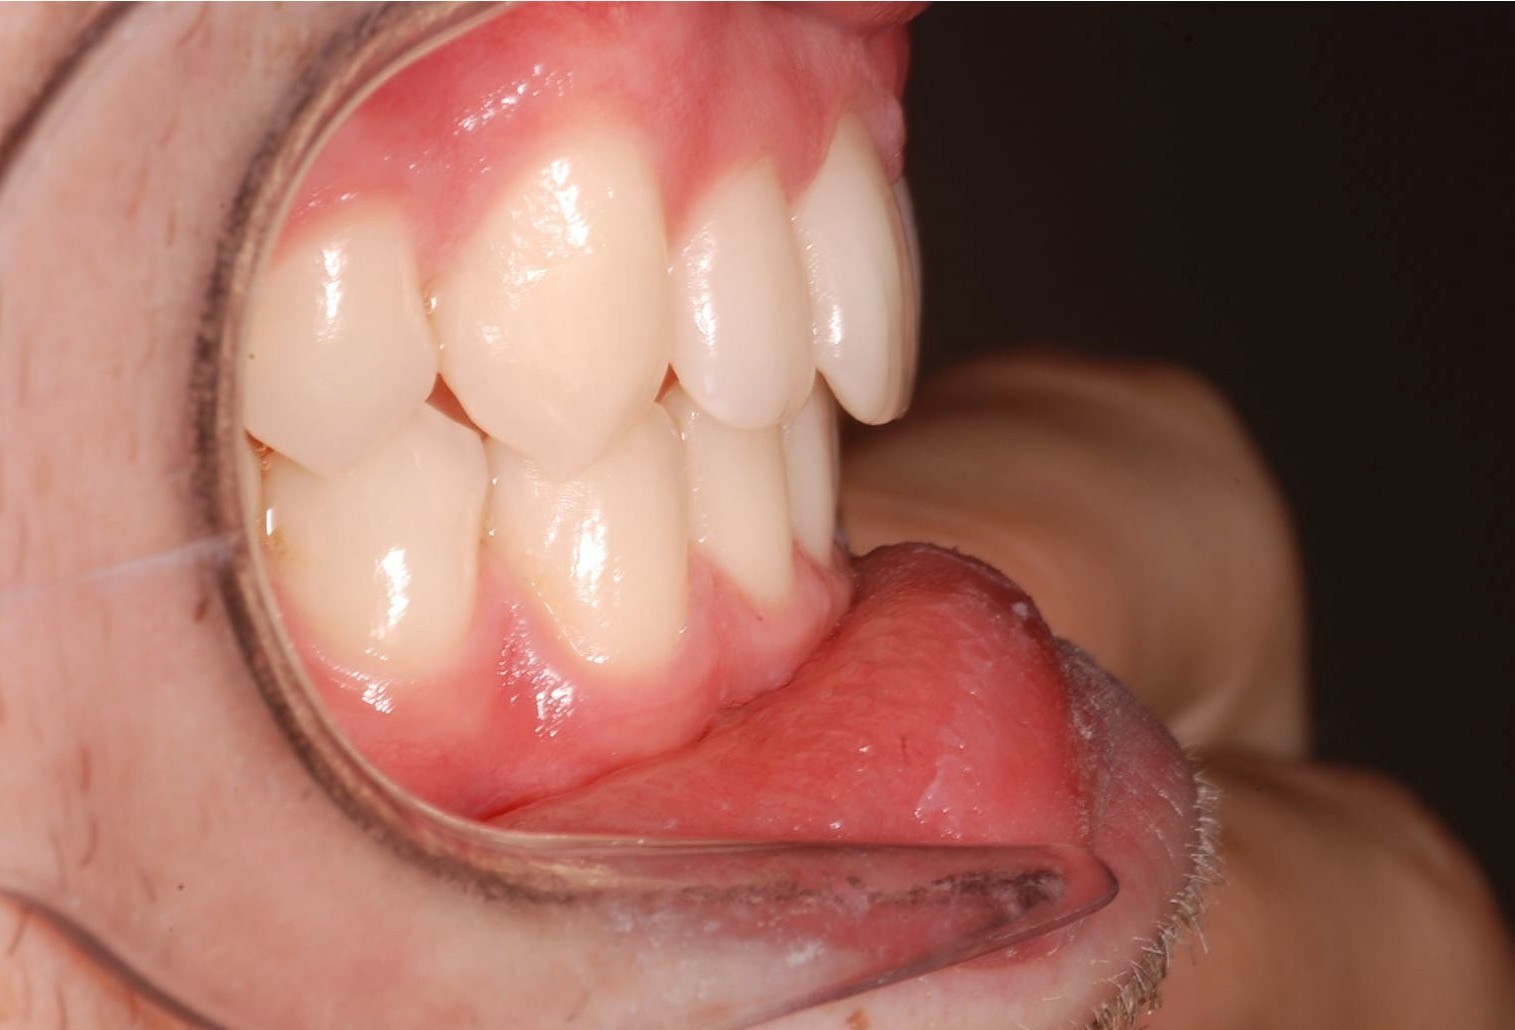

Class II subdivision malocclusions can be difficult to treat because of their asymmetric occlusal relationships. An accurate diagnosis, etiologically based when possible, is essential to perform a correct and efficient orthodontic treatment.

The aim of this article is to illustrate a case report treated with customized lingual brackets in association with a simple vestibular device.